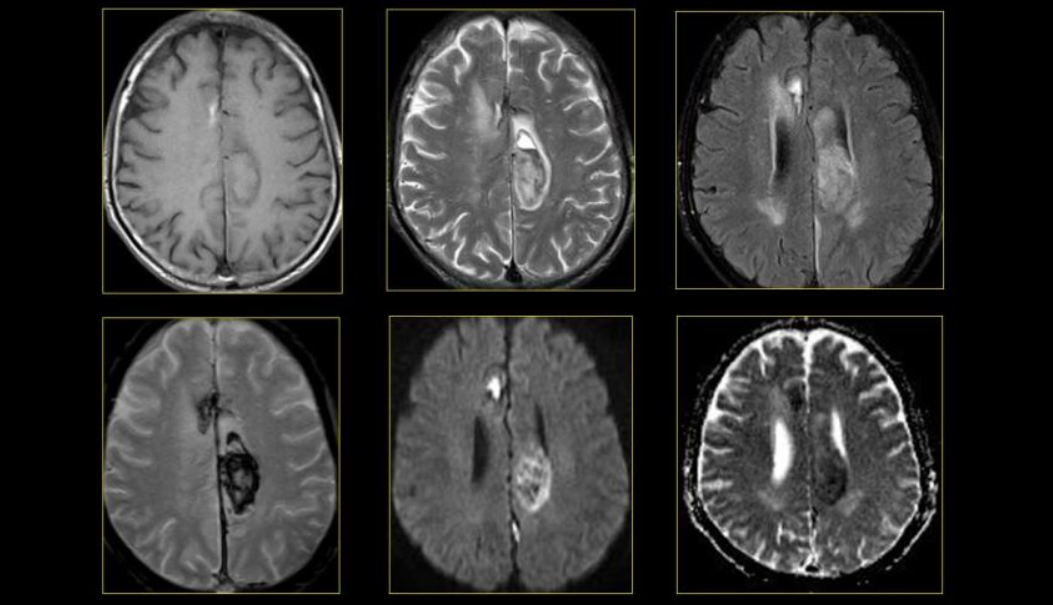

3.1 MRI của Não và tủy sống

MRI là phương pháp xét nghiệm hình ảnh được sử dụng thường xuyên nhất đối với não và tủy sống. MRI thường được thực hiện để giúp chẩn đoán:

- Chứng phình động mạch não

- Rối loạn của mắt và tai trong

- Đa xơ cứng

- Rối loạn tủy sống

- Ảnh hưởng do chấn thương

- Khối u

- Chấn thương sọ não do va chạm

Một loại MRI đặc biệt - MRI chức năng của não (fMRI), có thể tạo ra hình ảnh của lưu lượng máu đến các khu vực nhất định của não. Nó có thể được sử dụng để kiểm tra giải phẫu não và xác định phần nào của não đang xử lý các chức năng quan trọng.

Điều này giúp xác định các khu vực kiểm soát chuyển động và ngôn ngữ quan trọng trong não của những người được xem xét phẫu thuật não. MRI chức năng cũng có thể được sử dụng để đánh giá thiệt hại do Chấn thương đầu hoặc do các rối loạn như bệnh Alzheimer.